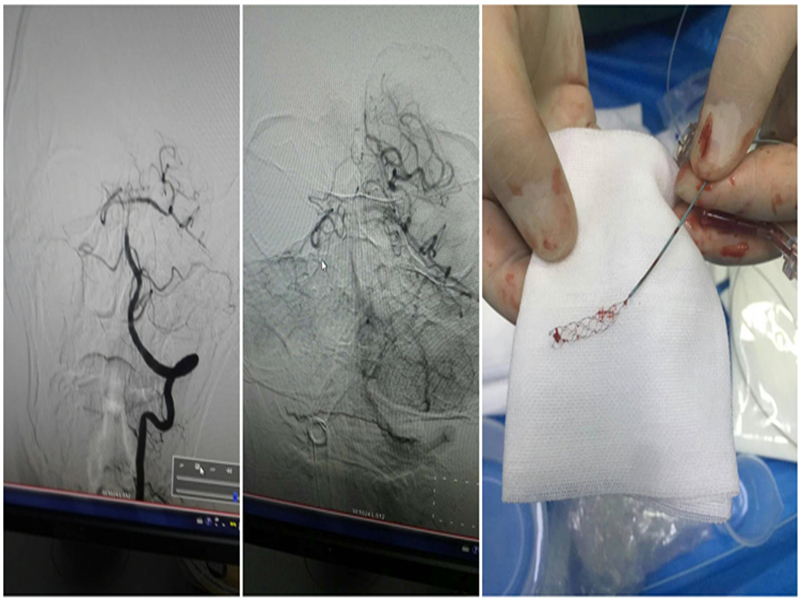

69 2 25 A1 MTICI 3